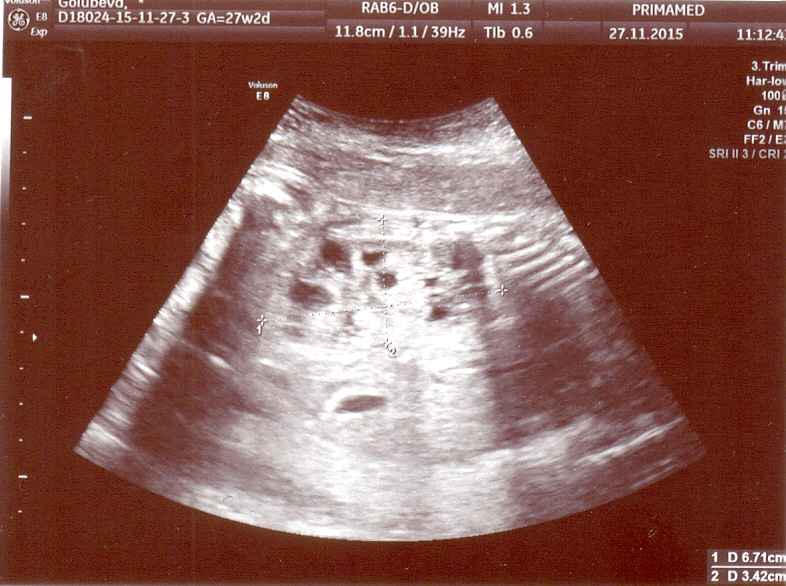

Спасибо доктор, немного утешили!Все станет ясно завтра-консилиум.И я так понимаю,что поликистоз все-таки,если можно так сказать лучше чем мультикистоз.А так почки увеличены правая-64*40,а левая-67*34,паренхима с множественными мелкокалиберными кистами.БПР 73мм,ЛЗР-96мм,ОГ-268мм,ОЖ-249мм ДБ-49мм.

Михаил Юдович,прикрепляю снимки.Заранее благодарна!Вы дали нам надежду и может сегодня ночью я посплю.Да кстати мне 39 лет и это мои 2 роды,первому ребенку 16 лет и никаких проблем с почками у него нет.Хотя у меня до 1-й беременности один раз были проблемы -в 1998году и что-то там было( 1 почка увеличена и раздвоена).Но после этого ни разу за 16 лет я про почки не вспоминала,еще у меня резус отрицательный у мужа положительный.Может какие-то из этих признаков повлияли на эту патологию?

3olg76uyar, Выскажу своё мнение, которое не является окончательным заключением, т.к. УЗИ надо видеть "в живую" Я думаю, это не мультикистоз, а другое, также очень тяжёлое заболевание. Это больше похоже на неонатальный тип поликистоза почек. Почки очень большие. Я смог разглядеть надпись - они по 6 см в длину. Это размер почек годовалого ребёнка. Паренхима в почках есть (что исключает мультикистоз), но она очень гиперэхогенная и высока вероятность продвинутой почечной недостаточности с рождения. Столь большие почки снизу давят на лёгкие и могут вызвать их недоразвитие. Подобный тип поликистоза почти всегда сопровождается фиброзом печени, который может быть пока не виден по УЗИ, но прогрессирует в течение нескольких лет после рождения.

Здравствуйте!Сегодня был консилиум и диагноз мультикистозная дисплазия обеих почек подтвердился.Правая почка-61*35,левая-65-32,ткань перенхимы почек представлена множеством анехогенных включений Д до 13мм. Мочевой пузырь 20*15.ИАЖ-8 см.Беременность 28 недель.При этом все остальные органы в норме без потологий.Следующий консилиум через 3 недели и я так понимаю шансов практически нет.